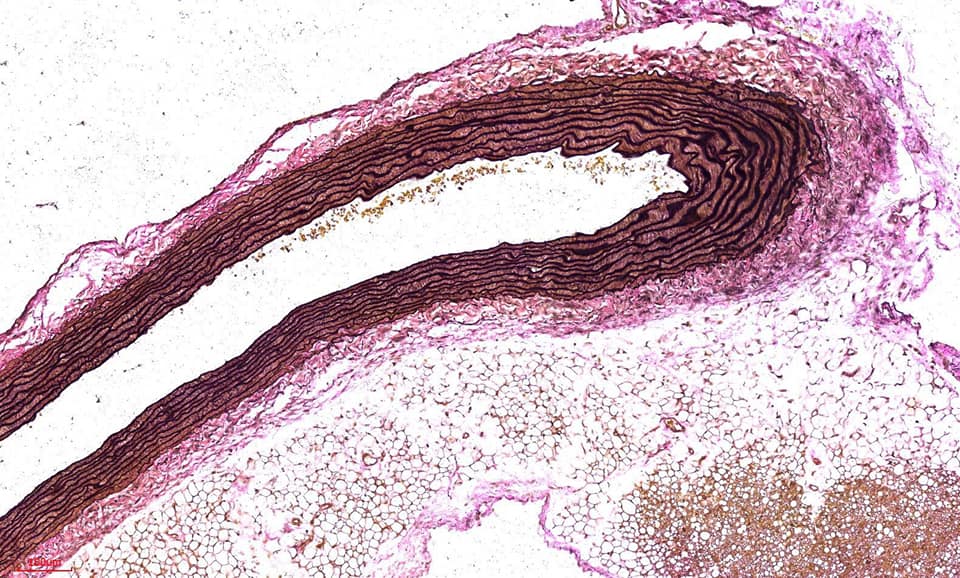

彈力纖維(Verhoeff’s Van Gieson,EVG)染色,彈性纖維廣泛分佈與身體各處,特別在動脈壁、肺泡壁和皮膚中最為豐富。觀察組織內彈性纖維是否有增生或斷裂崩解等。

Miller’s Elastic Stain ( E.V.G stain) 實際染色範例

※結果觀察:

彈力纖維呈藍黑色,肌纖維、纖維素、神經膠質呈黃色,膠原纖維呈紅色,胞核呈藍色